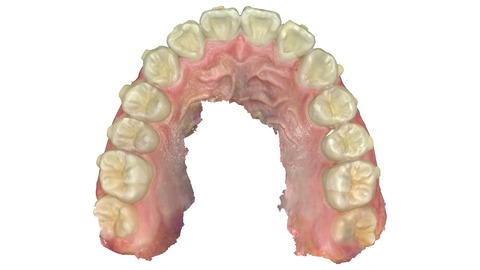

2025年1月5日 わずか9か月後の状態。

上の歯。引っ込んだ歯が歯並びの中に納まっている。

上の歯の比較